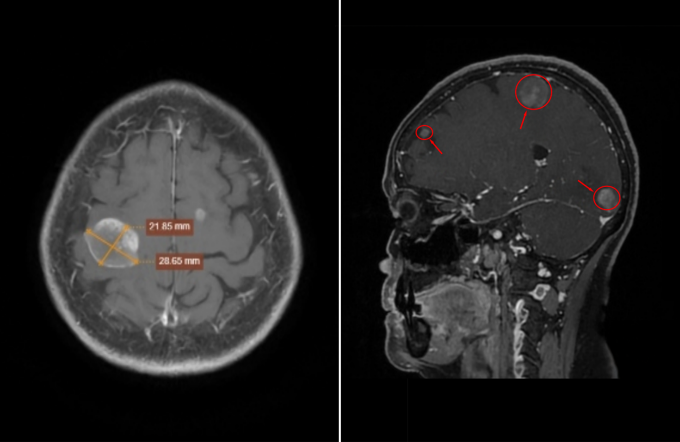

BS.CKII Nguyễn Văn Phúc, Trưởng khoa Chẩn đoán hình ảnh, xem hình ảnh MRI nghi ngờ các khối u thứ phát, tức có thể di căn từ cơ quan khác trong cơ thể. Một số khối có kích thước rõ như khối ở thùy chẩm phải khoảng 18×19 mm và khối ở thùy đỉnh phải khoảng 21×28 mm. Song, cấu trúc não vẫn giữ vị trí bình thường, chưa ghi nhận dấu hiệu chèn ép nên người bệnh chưa xuất hiện triệu chứng thần kinh rõ ràng.

Ảnh chụp MRI não bằng hệ thống 3 Tesla Signa Hero cho thấy các khối u di căn xuất hiện tại não. Ảnh: Phòng khám Đa khoa Tâm Anh Quận 7